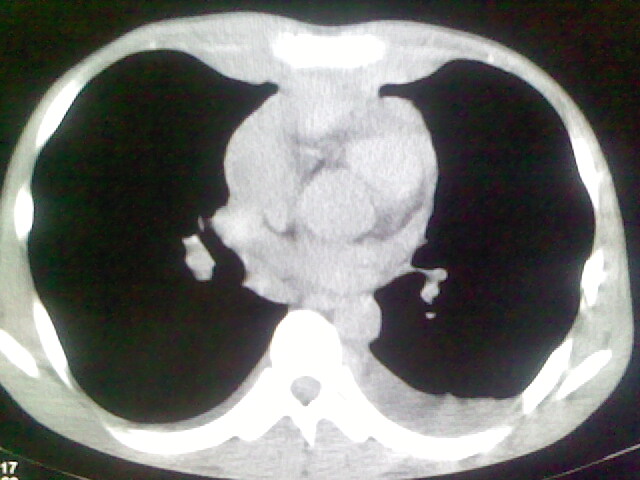

以下是引用杀毒软件在2008-9-3 6:11:00的发言:[br]侵袭性胸腺瘤------一般不侵到气管旁[br][br]考虑----纵隔淋巴瘤,心包及胸膜受累

以下是引用随光逐影在2008-9-3 7:07:00的发言:[br]1)考虑淋巴瘤可能。2)双侧胸腔积液(以左侧为甚)。3)心包积液。